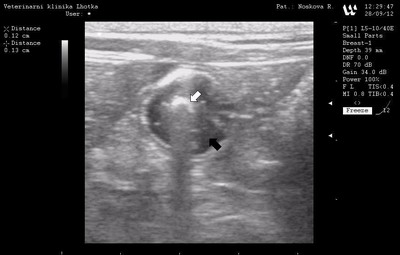

Ultrasonografické vyšetření dutiny břišní, rovněž potvrdilo přítomnost cizího tělesa (bílá šipka) a patologické hromadění tekutiny (černá šipka) ve střevě. Naštěstí vyšetření neobjevilo volnou nitrobřišní tekutinu, která by mohla indikovat perforaci trávícího traktu.

Ultrasonografické vyšetření dutiny břišní Ultrasonografické vyšetření dutiny břišní